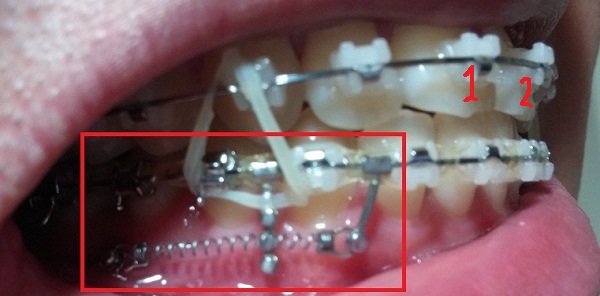

-하악 파워체인 엇갈려서 걸어놓기(후기 23화와 같은 치료),

-하악 스프링 + 덧대기(잇몸이 눌리지 않게)

[스프링 옆면]

+스프링사이에 또 다른 쇠기둥 보이시죠?! 저건 스프링이 잇몸에 닿아서 짓눌리지 않게 하기 위해서 해둔 조치랍니다.(제가 눌려서 아프다고 호소했더니 저런 방법으로 해주셨어용^^)

[스프링아래서 본]